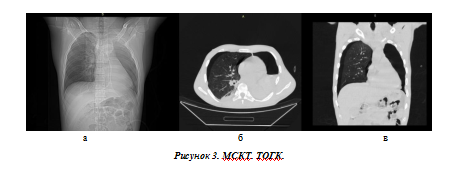

На топограмме (а) хорошо визуализируется тотальный пневматоракс слева. На аксиальном срезе (б) кроме пневмоторакса определяется и гемоторакс (горизонтальный уровень жидкости). На фронтальном срезе можно увидеть, что воздух имеется и в плевральной полости правого легкого.